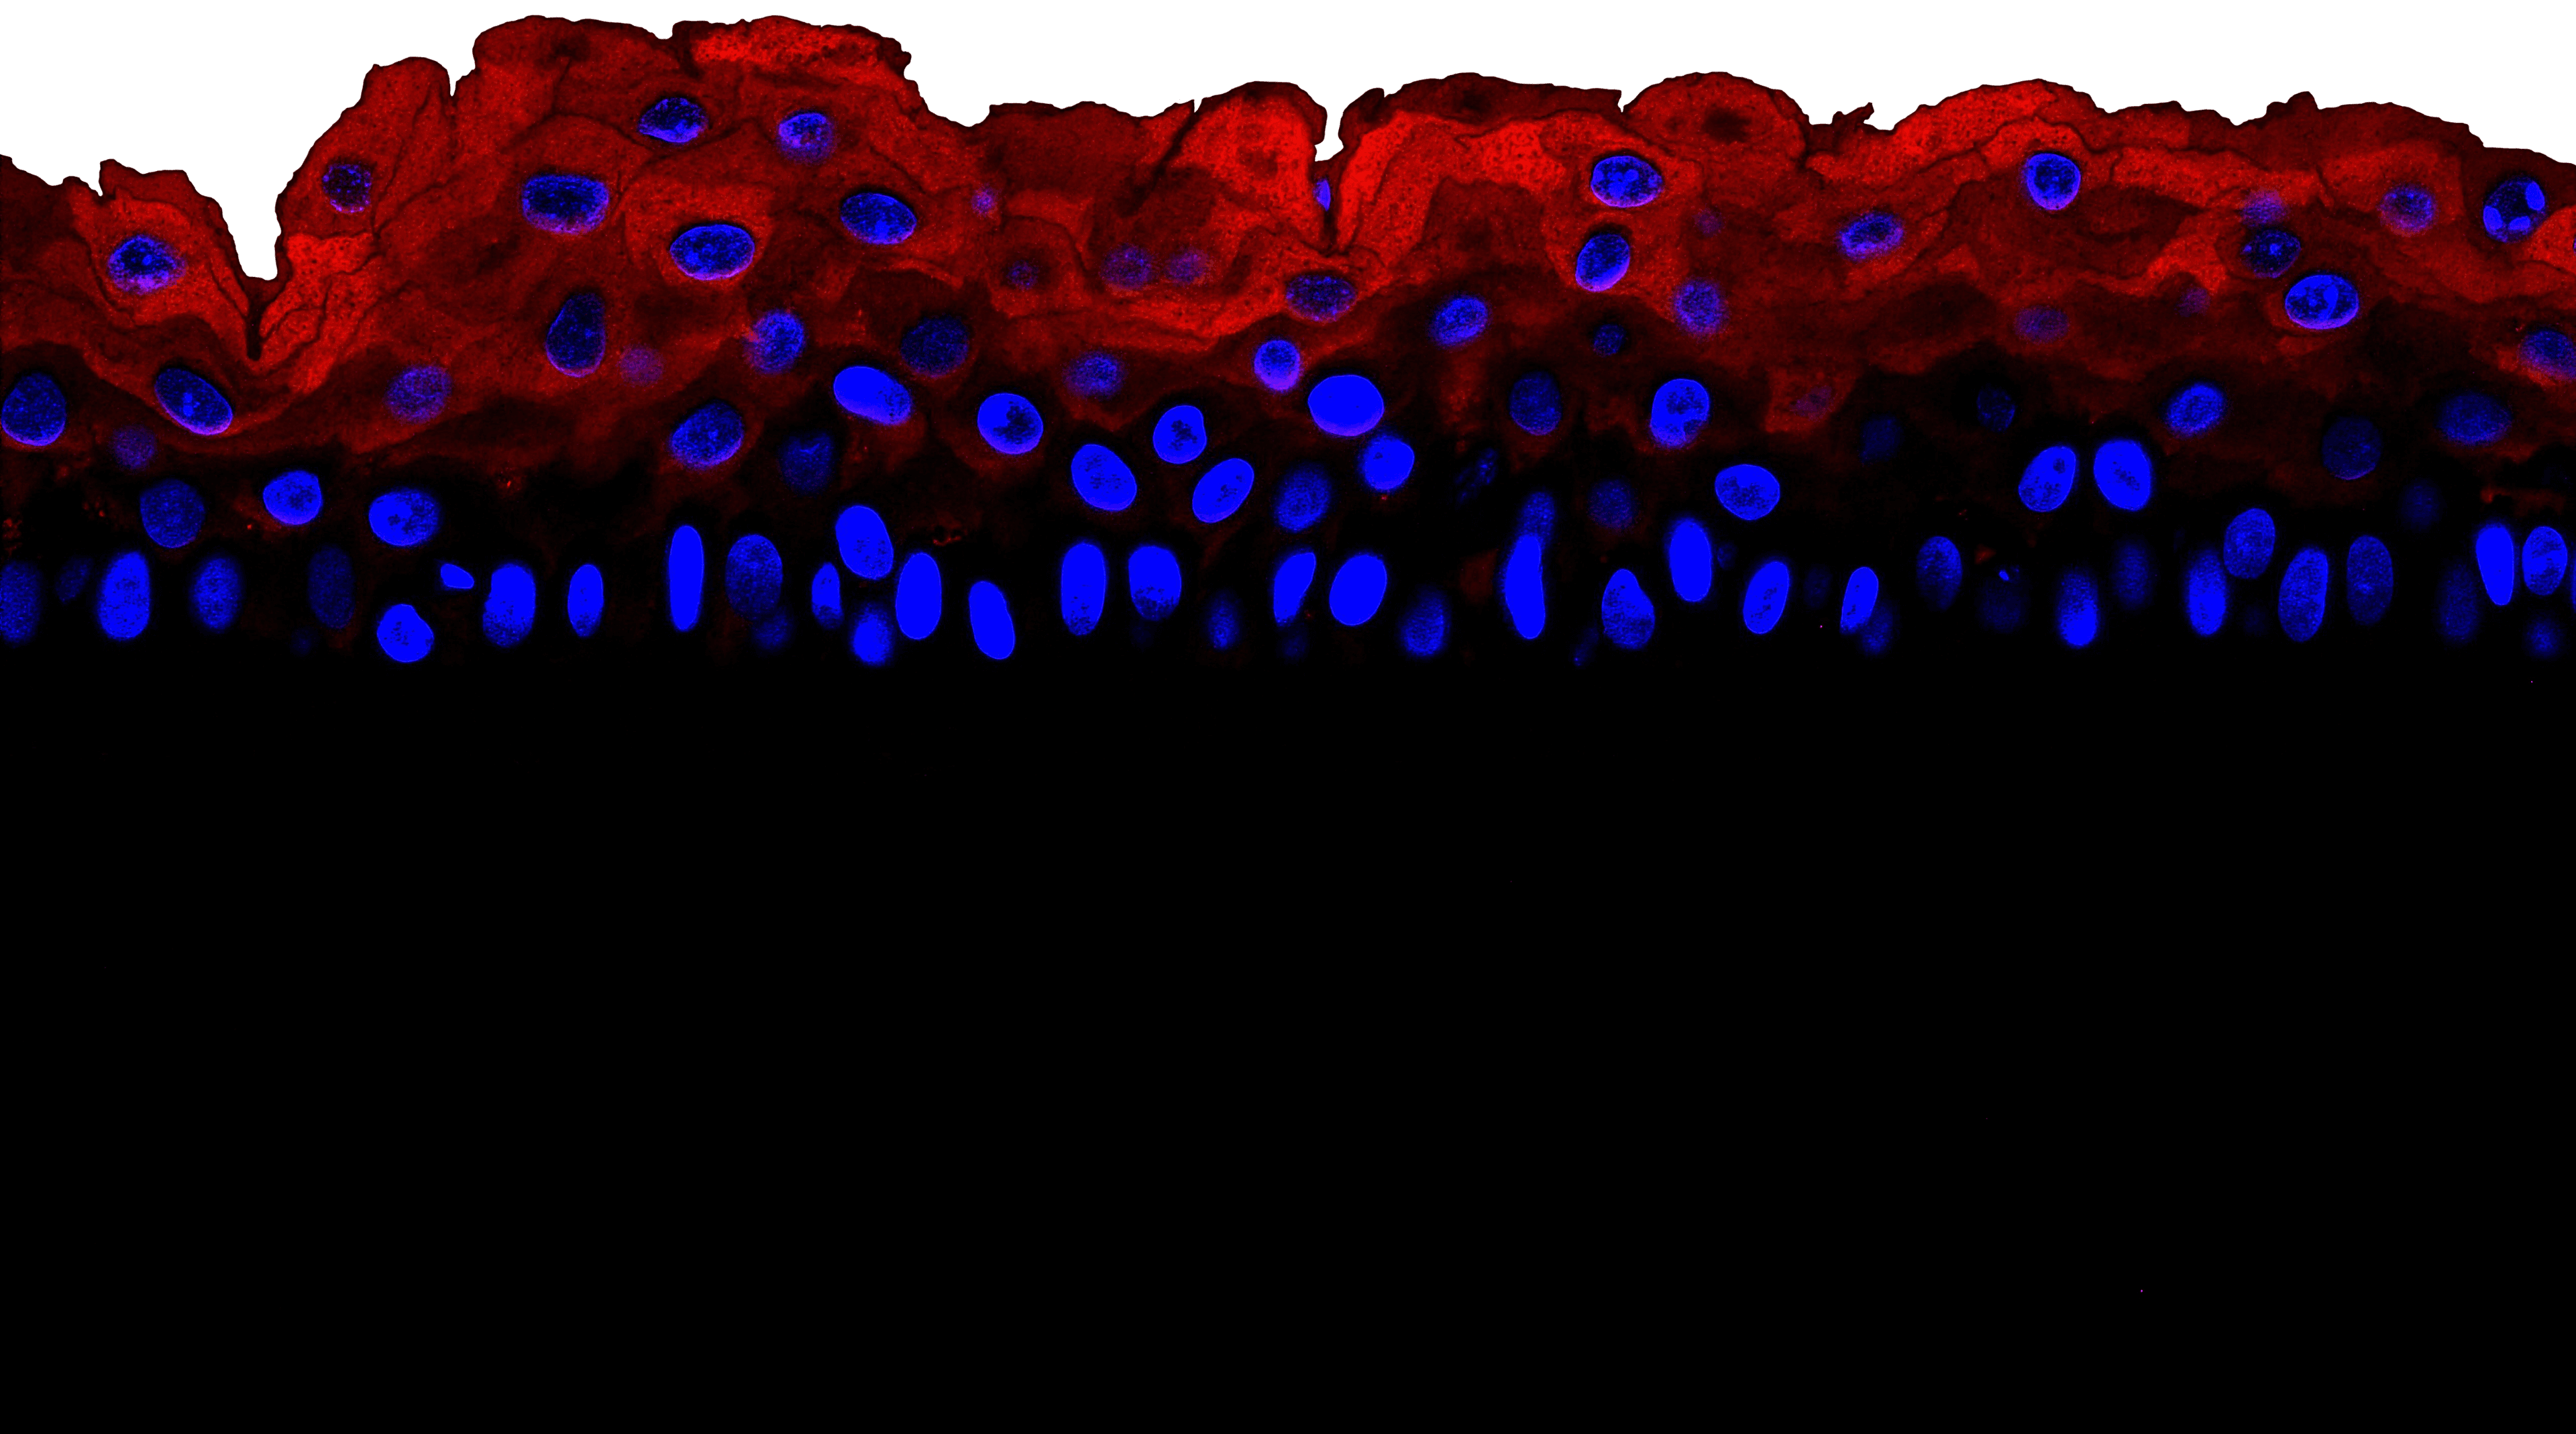

VitroScreen, a SenzaGen Group company, pioneers next-generation in vitro testing solutions. We leverage cutting-edge biological models—from 2D cells and reconstructed tissues to ex vivo systems and cellular spheroids—to deliver precise, human-relevant data for the Cosmetics, Medical devices, Nutraceuticals, Pharma and Chemicals industries.

Our models mirror human biology for precise, predictive accuracy.

VitroScreen, a longstanding leader in sophisticated in vitro assays, propels the transition from animal-based paradigms to human-relevant models with unwavering ethical commitment. Integration with SenzaGen has amplified our technological prowess and international footprint, enabling delivery of expansive, high-fidelity services. This alliance fortifies our vanguard role in non-animal testing innovation.

We design and execute rigorous preclinical in vitro studies, combining validated testing standards with fully customized protocols to deliver reproducible, decision-ready results. Our expertise covers multiple product categories and therapeutic areas, providing highly predictive platforms for both regulatory and efficacy assessment.